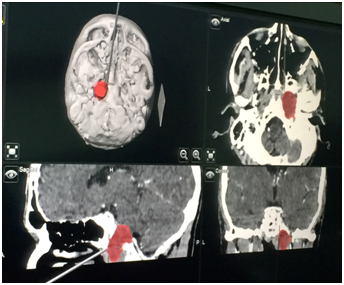

A 43years old man presented with 6month history of intermittent right hemicranial headache and ipsilateral conductive hearingloss. The patient had no historyof head trauma. The MRI demonstrated a large and expansile right petrous apex lesion hyper intense on both T1- and T2-weighted scans, without diffusion restriction or internal contrast enhancement. The CT scan showed and expansile and lyticlesion with surrounded bony erosion (Figures 1-4).

Figure 1 A large expansile lesion is noted in the right petrous apex, hyper intense on both T1- and T2-weighted scans, without diffusion restriction or internal contrast enhancement.

Figure 4 Image Guidance screen shot showing right petrous Apex lesion.